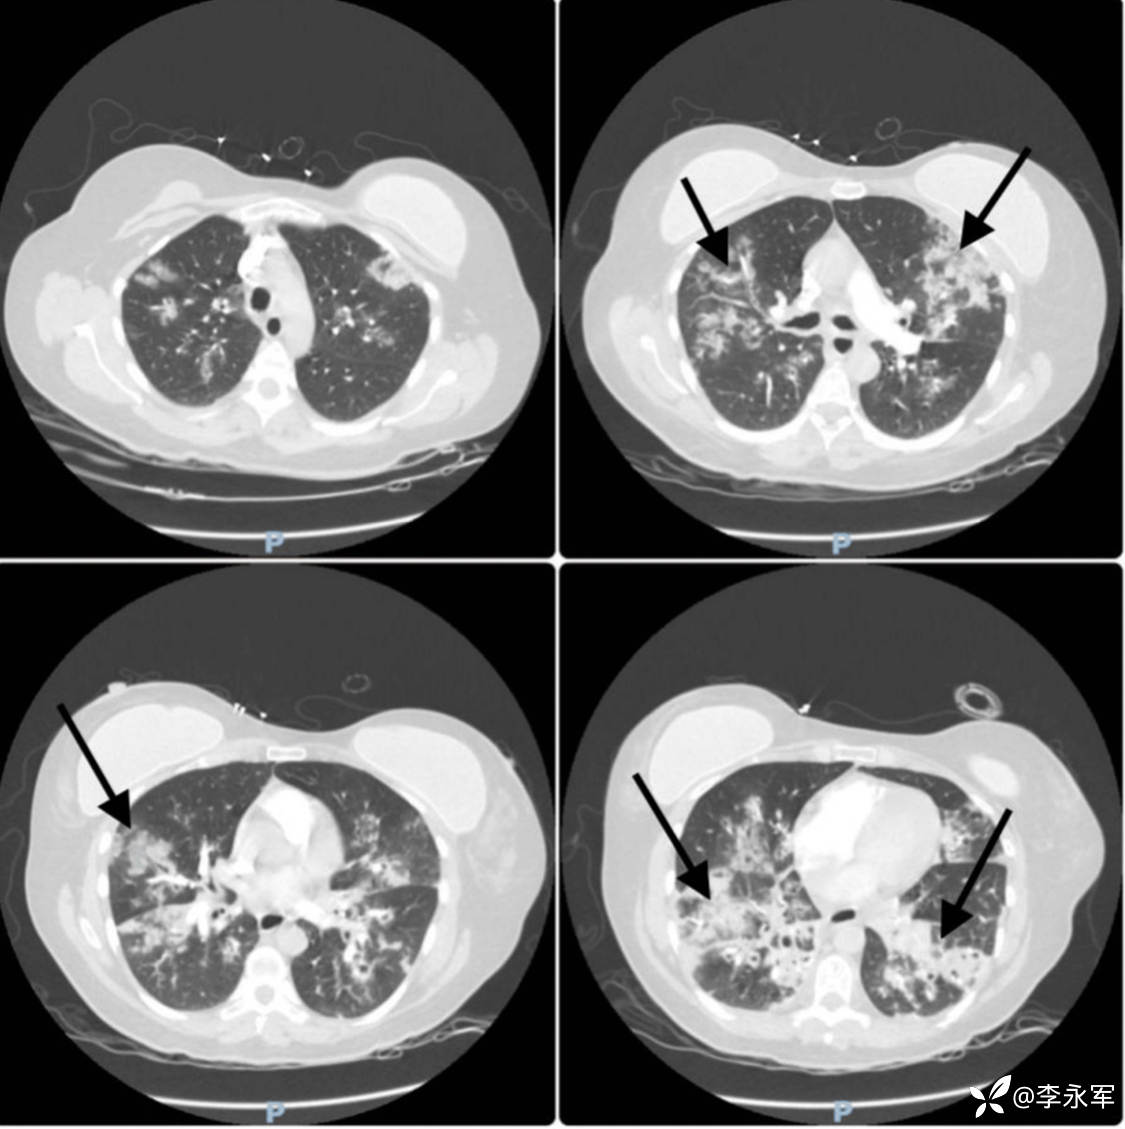

高流量鼻导管氧疗下的复查动脉血气显示呼吸性碱中毒缓解,氧合改善(PaO2 = 73 mmHg,SpO2 = 95%)。听诊显示双侧呼吸音清晰,伴弥漫性干啰音。复查胸部 X 光片和 CT 扫描显示双侧斑片状浸润影,符合 ARDS 表现,并怀疑叠加细菌感染。实验室结果显示 CRP 显著升高至 283.9 mg/L,白细胞计数下降至 3.33 x 10^9/L。考虑到她的 PaO2/FiO2 比值为 73(在使用 100% FIO2 和 60 升/分钟流速下),符合更新版全球定义中 ARDS 的诊断标准。

图 3:入院时胸部 CT